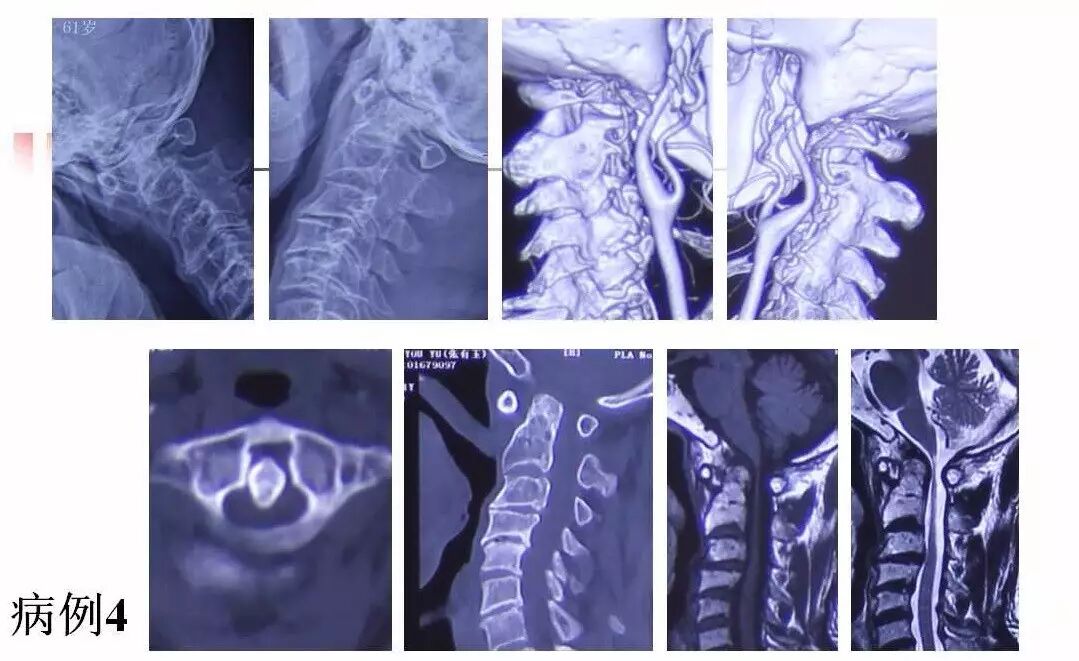

在脊柱神经外科、显微神经外科和颅底肿瘤外科前沿研究和临床诊治领域有着扎实的基础,为全国首批获得脊柱神经外科医师培训认证的神经外科医生。擅长颈椎病、椎管肿瘤及各种脊柱疑难疾病的诊治、脑肿瘤微创手术,尤其擅长颈椎退行性疾病的手术,率先在国内开展了颅底凹陷后路复位、颈前路减压融合等高难度手术,多年来收治了来自全国各地的大量患者,疗效达到国内领先水平。